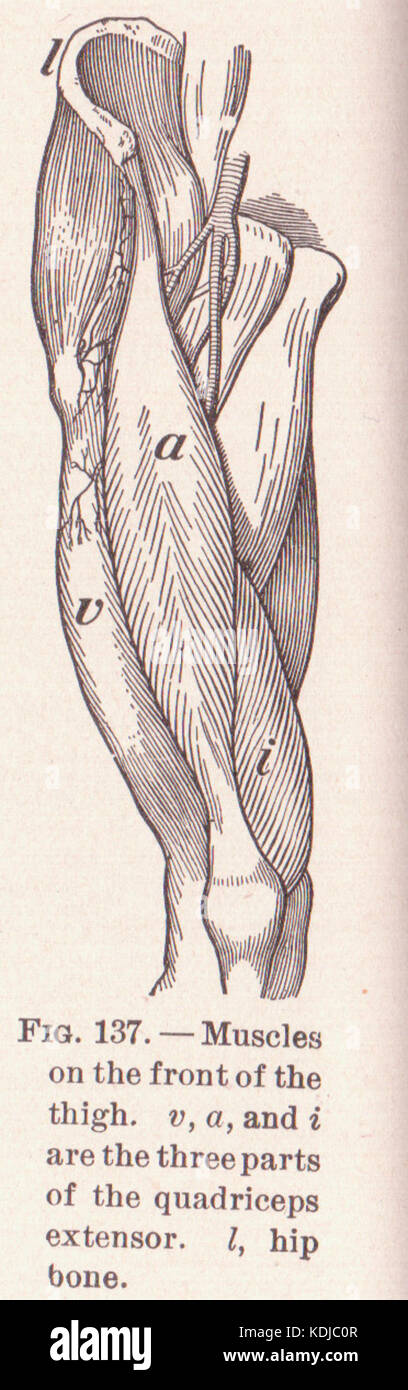

Les muscles du Thigh, également connus sous le nom de quadriceps, sont les muscles les plus forts et les plus poiles du corps humain. Ce sont des extenseurs majeurs du genou, drawi vintage ligne Illustration de Vecteurhttps://www.alamyimages.fr/image-license-details/?v=1https://www.alamyimages.fr/les-muscles-du-thigh-egalement-connus-sous-le-nom-de-quadriceps-sont-les-muscles-les-plus-forts-et-les-plus-poiles-du-corps-humain-ce-sont-des-extenseurs-majeurs-du-genou-drawi-vintage-ligne-image367217740.html

Les muscles du Thigh, également connus sous le nom de quadriceps, sont les muscles les plus forts et les plus poiles du corps humain. Ce sont des extenseurs majeurs du genou, drawi vintage ligne Illustration de Vecteurhttps://www.alamyimages.fr/image-license-details/?v=1https://www.alamyimages.fr/les-muscles-du-thigh-egalement-connus-sous-le-nom-de-quadriceps-sont-les-muscles-les-plus-forts-et-les-plus-poiles-du-corps-humain-ce-sont-des-extenseurs-majeurs-du-genou-drawi-vintage-ligne-image367217740.htmlRF2C9C5Y8–Les muscles du Thigh, également connus sous le nom de quadriceps, sont les muscles les plus forts et les plus poiles du corps humain. Ce sont des extenseurs majeurs du genou, drawi vintage ligne

Cette image ou référence de la page 206 met en évidence l'anatomie des muscles de la cuisse, en se concentrant sur les muscles clés impliqués dans le mouvement et leurs fonctions dans le corps humain. Banque D'Imageshttps://www.alamyimages.fr/image-license-details/?v=1https://www.alamyimages.fr/photo-image-cette-image-ou-reference-de-la-page-206-met-en-evidence-l-anatomie-des-muscles-de-la-cuisse-en-se-concentrant-sur-les-muscles-cles-impliques-dans-le-mouvement-et-leurs-fonctions-dans-le-corps-humain-163288407.html

Cette image ou référence de la page 206 met en évidence l'anatomie des muscles de la cuisse, en se concentrant sur les muscles clés impliqués dans le mouvement et leurs fonctions dans le corps humain. Banque D'Imageshttps://www.alamyimages.fr/image-license-details/?v=1https://www.alamyimages.fr/photo-image-cette-image-ou-reference-de-la-page-206-met-en-evidence-l-anatomie-des-muscles-de-la-cuisse-en-se-concentrant-sur-les-muscles-cles-impliques-dans-le-mouvement-et-leurs-fonctions-dans-le-corps-humain-163288407.htmlRMKDJC0R–Cette image ou référence de la page 206 met en évidence l'anatomie des muscles de la cuisse, en se concentrant sur les muscles clés impliqués dans le mouvement et leurs fonctions dans le corps humain.